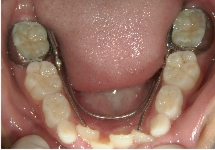

リンガルアーチ

主に奥歯の6番目の傾斜を立てなおしたり、ねじれた歯をもとに戻す際に使用する装置です。この症例の場合、舌側へ傾斜していた大臼歯が、装置の力で正常な位置まで起き上がりました。